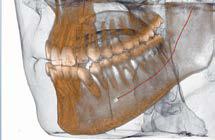

Nell’ambito della radiologia 3D ortopedica, il centro diagnostico utilizza il nuovissimo macchinario NewTom 5G XL, in grado di individuare con la massima precisione la presenza di fratture o lussazioni delle articolazioni, controllare la corretta guarigione di una frattura, valutare una lesione o una ferita causata da infezione, artrite o crescita anormale dell’osso.

Se con la radiologia tradizionale era necessario eseguire scansioni multiple, la novità introdotta dal macchinario NewTom 5G XL risiede nella capacità di fornire immagini ad alta risoluzione in un’unica scansione, mostrando nitidamente i dettagli delle articolazioni degli arti superiori e inferiori. Inoltre, a differenza della tecnologia 2D, la radiologia 3D ortopedica permette di individuare immediatamente alcune patologie come quella del metatarso, la quale richiede un allineamento visivo dedicato o una diagnosi delle micro fratture ossee.